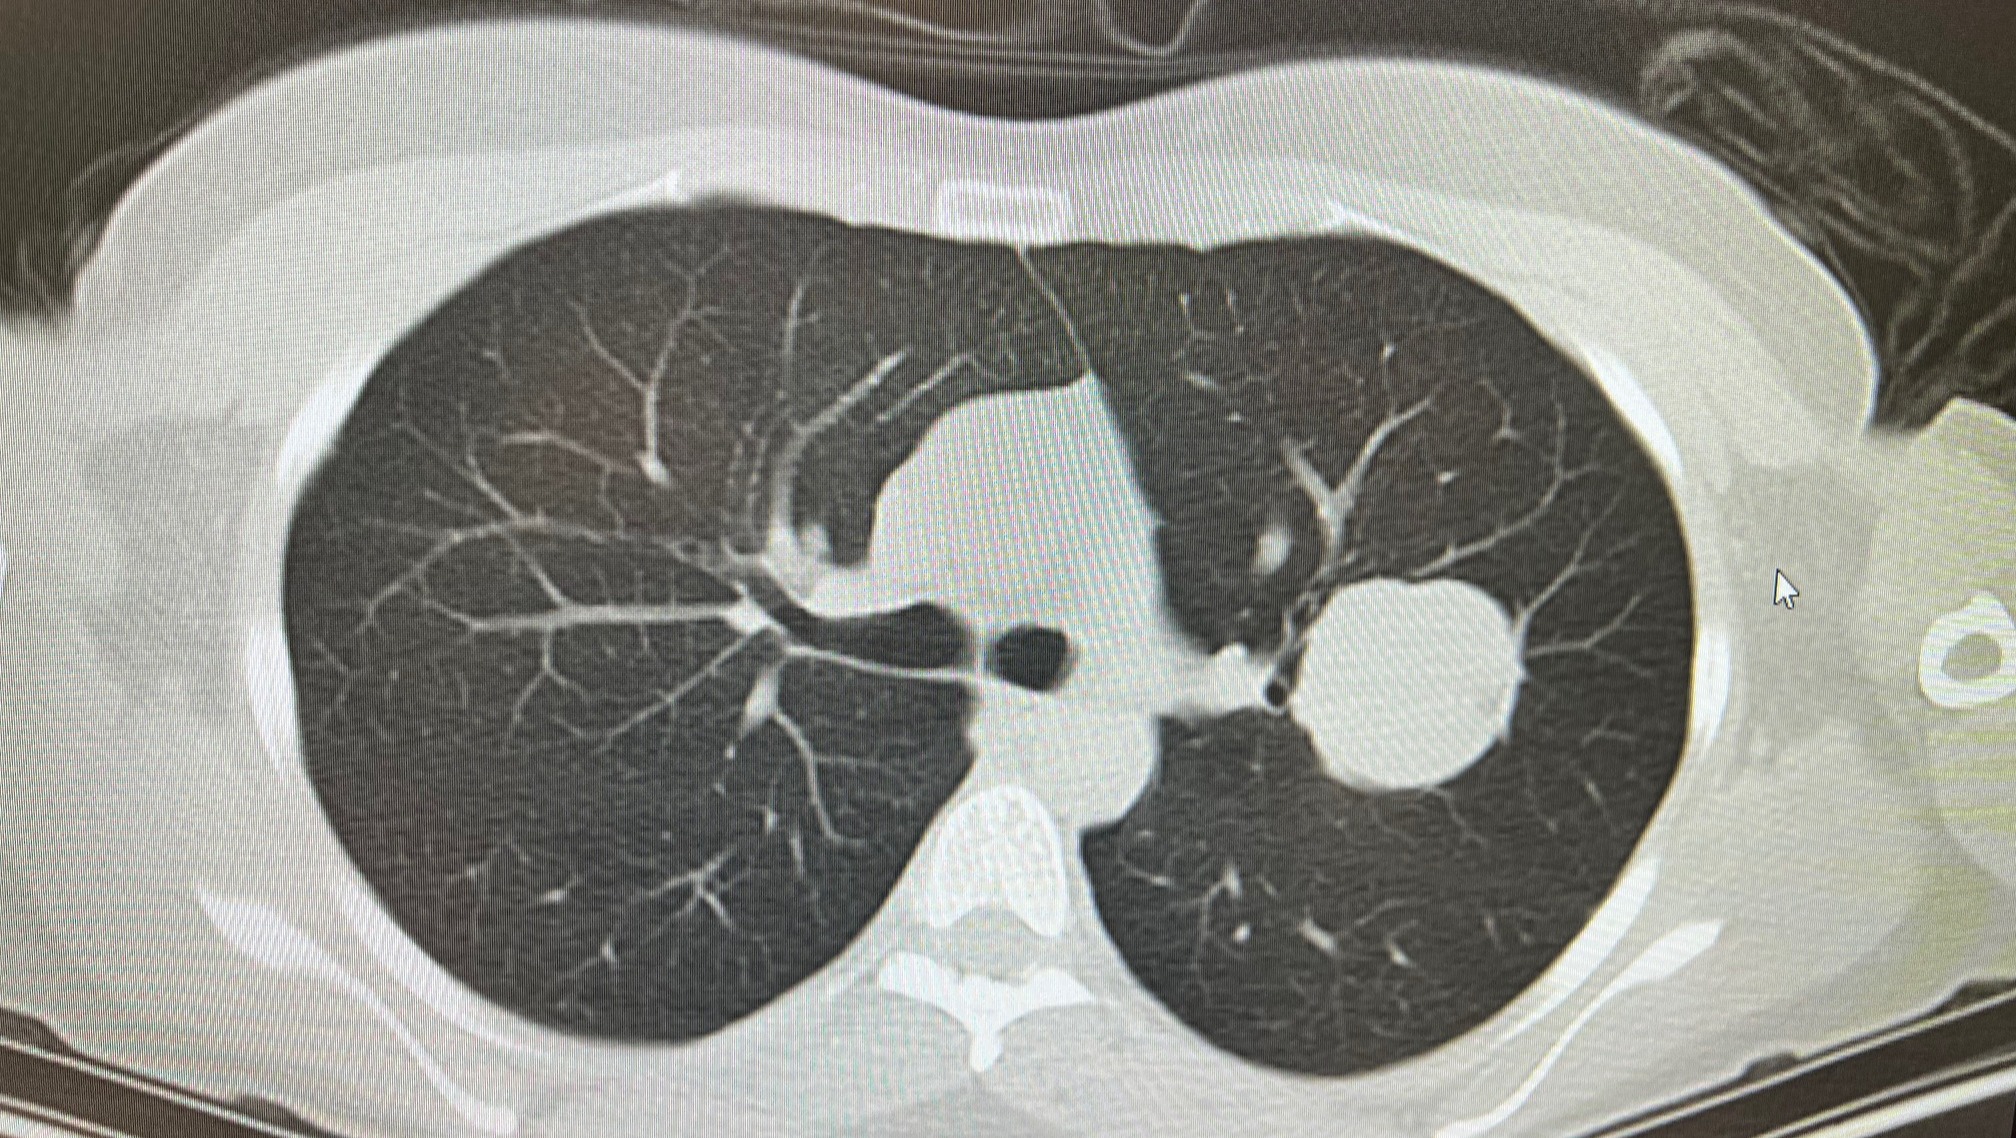

Last fall she noticed chest pain, and her doctors discovered a baseball-sized tumor in her lung. The surgery to remove the tumor also removed the entire upper left lobe of her lung.

^ An actual picture of the tumor discovered in Erin's lung, which she's taken to calling her "poison apple."